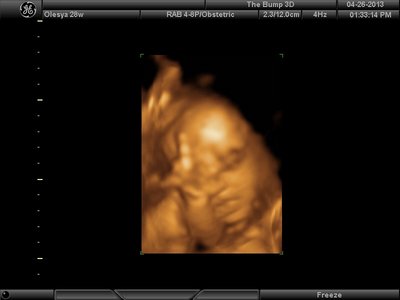

А я вчера на 3Д УЗИ ходила. Моя звезда закрывалась в еми 4мя конечностями. Просто пополам сложилась и спала себе сладко. УЗИстка провела со мной час, кое-как расшевелили маленькую, но ручка была постоянно на мордашке и засыпала она почти сразу снова. Я и на мяче прыгала и живот трясла. В конце более-менее фото вышли, но качество меня не порадовало. Возможно фри оф чардж еще раз переделают. Со средней фотки были отличного качества, а эти сплошное разочарование. Вот тут что-то более-менее еще. Главное пальчик оттопырила так смешно, мол минуточку. Вообще немного жутковатые фотки..хаха

Вложения: |

image.jpg [ 47.86 КБ | Просмотров: 1184 ]